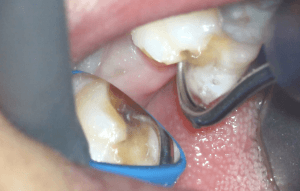

金属を除去してみると大きな虫歯が確認できました。

遠心方向からタービンなどの切削器具を用いる場合はミラーテクニックを併用します。特にエナメル質を保存する場合はアンダーカット部の軟化象牙質の除去にはエアースケーラーのラウンドチップを用いての除去が優れていて使いやすいと思います。